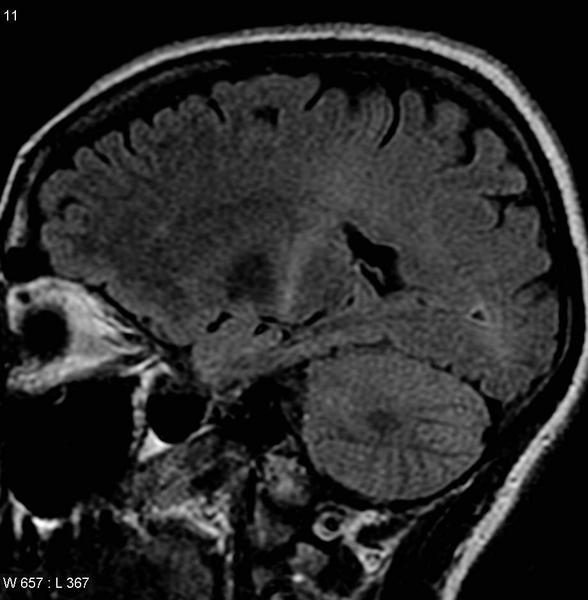

Cerebro afectado por la ELA

Un proyecto del Consejo Superior de Investigaciones Científicas (CSIC) ha recibido una ayuda Starting Grant del Consejo Europeo de Investigación (ERC) dotada de 1,5 millones. Durante cinco años, el equipo del investigador del Instituto de Química Física Rocasolano (IQFR-CSIC) Miguel Mompeán desentrañará las reglas que determinan que ciertas proteínas se asocien para formar complejos biomoleculares relacionados con enfermedades neurodegenerativas como el alzhéimer o la Esclerosis Lateral Amiotrófica ELA. Conocer cómo ocurren los procesos de apilamiento y asociación de proteínas abrirá las puertas a la prevención y al diseño de herramientas de diagnóstico precoz de estas patologías.